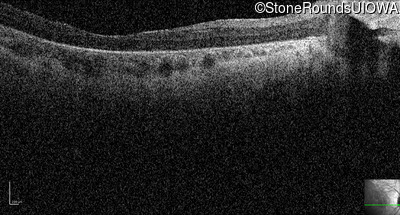

Optical Coherence Tomography - Left - 20/500 sc

Exemplar / OCT Stack